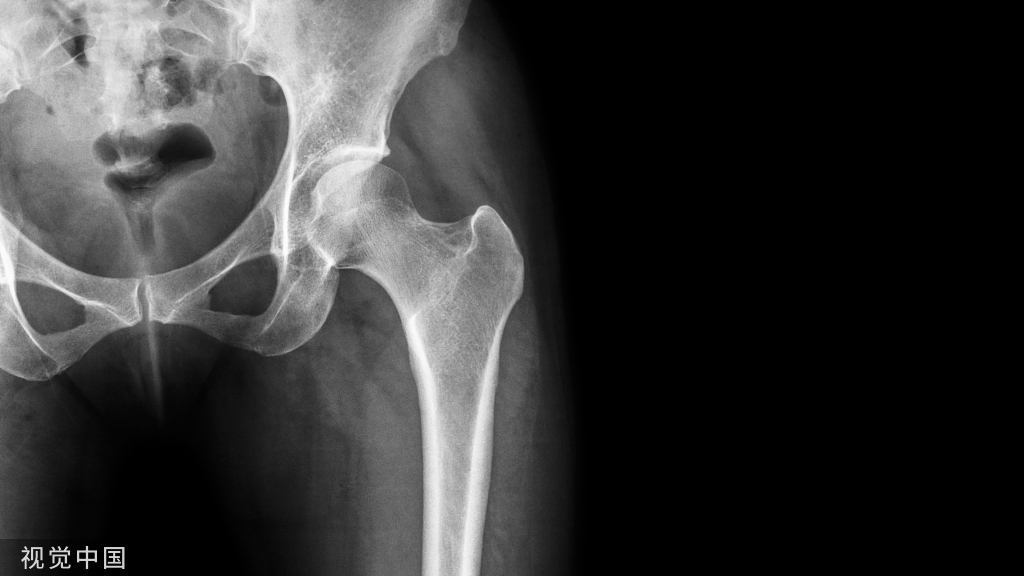

股骨近端髓腔类型与柄的选择

- Dorr分类法

- TypeA型:股骨髓腔在正位片上显示较厚的内外侧皮质,在侧位上显示较厚的后侧皮质,远端股骨髓腔较狭窄,因此近端髓腔呈漏斗形(Funnel)。

- TypeB型:股骨髓腔内侧尤其后侧皮质变薄,髓腔变宽

- TypeC 型:股骨髓腔内后侧皮质基本丢失,股骨髓腔显著增宽。形态如烟囱(Stovepipe).

漏斗指数:

- A型适合生物固定

- B型两者皆可使用

- C型适合水泥固定